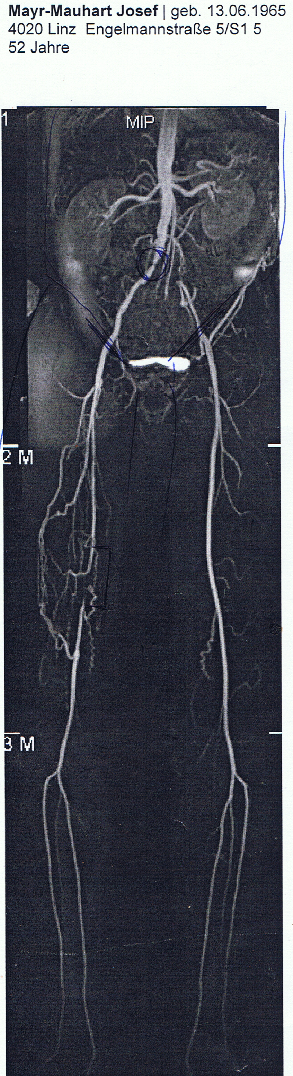

Derzeit sind die Zehen ziemlich blau und fahre heute

21.3.2018  jezt zur Einweisung bei den Brüdern.